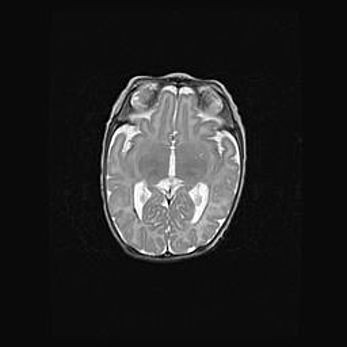

Множественные кисты обоих полушарий головного мозга, наибольшая из них в правой затылочной области. Ассиметричная атрофическая гидроцефалия.

Возраст: 7 месяцев

Вес: 5660 г

Пол: мужской

Окружность головы: 41,5 см

Срок гестации: 28-29 недель

Кисты головного мозга развиваются в результате многоочаговых некрозов вещества мозга и возникают вследствие перенесенной перинатальной инфекции, менингитов, энцефалитов, асфиксии, родовой травмы, расстройств мозгового кровообращения различного генеза. Образованию кист в веществе головного мозга плодов и новорожденных способствуют такие факторы, как высокое содержание в нем воды, недостаточная (или отсутствие) миелинизация и слабая астроглиальная реакция на повреждение.

Кисты могут сочетаться с гидроцефалией и другими поражениями головного мозга.